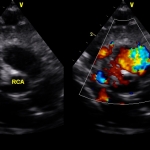

Υπερηχογράφημα (ECHO): φυσιολογική βασική ανατομία, φυσιολογικές διαστάσεις και λειτουργικότητα (συστολική και διαστολική λειτουργία, ελέγχθησαν και με ιστικό Doppler πέραν του συνήθους ελέγχου). Παρακάτω απεικονίζονται τα στεφανιαία. Ελέγχθηκε η έκφυση όχι μόνο με 2D, αλλά και με απεικόνιση της στεφανιαίας ροής με color Doppler (ασυνήθης πρακτική για παιδιά, θα εξηγηθεί ο λόγος στη συνέχεια).